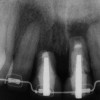

Figure 10  In these adjacent implants placed in the central and lateral positions, note the excellent interproximal bone but minimal interimplant distance.

Figure 10

Figure 11  Soft-tissue levels were acceptable at the time of placement of the final restoration.

Figure 11

Figure 12  At 6 months postinsertion, the papilla receded as bone was lost.

Figure 12

Figure 13  Twelve months after placement, soft tissue migrated apically as bone between the implants continued to resorb.

Figure 13